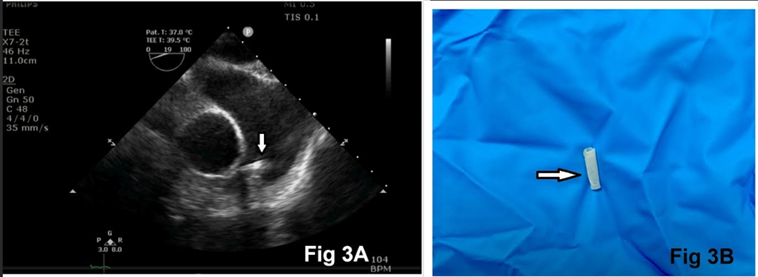

Utilizing pressure monitoring and waveform analysis, a 7.5F PAC was inserted through an 8.5F introducer sheath. After obtaining the right atrial pressure waveform at a depth of 20 cm, the balloon was inflated with a 1.5-ml syringe. However, the right ventricular pressure waveform could not be obtained until a depth of 30 cm. The balloon was deflated, and the PAC was retracted to 20 cm. During the second attempt to insert the PAC, the balloon failed to inflate, indicating a loss of resistance consistent with balloon rupture. Upon withdrawing the PAC from the sheath, it was noted that while the catheter remained intact, the balloon was notably missing (Fig. 2C). At this point, rupture of the balloon and its migration into the circulatory system were suspected. An immediate TEE evaluation showed the ruptured balloon floating in the main PA, just distal to the pulmonary valve.

Figure 3: Transesophageal echocardiography ascending aorta short-axis view showing embolized balloon in the main pulmonary artery (arrow), just distal to the pulmonary valve (Figure. 3A). Surgically retrieved balloon of the pulmonary artery catheter (arrow, Figure. 3B).